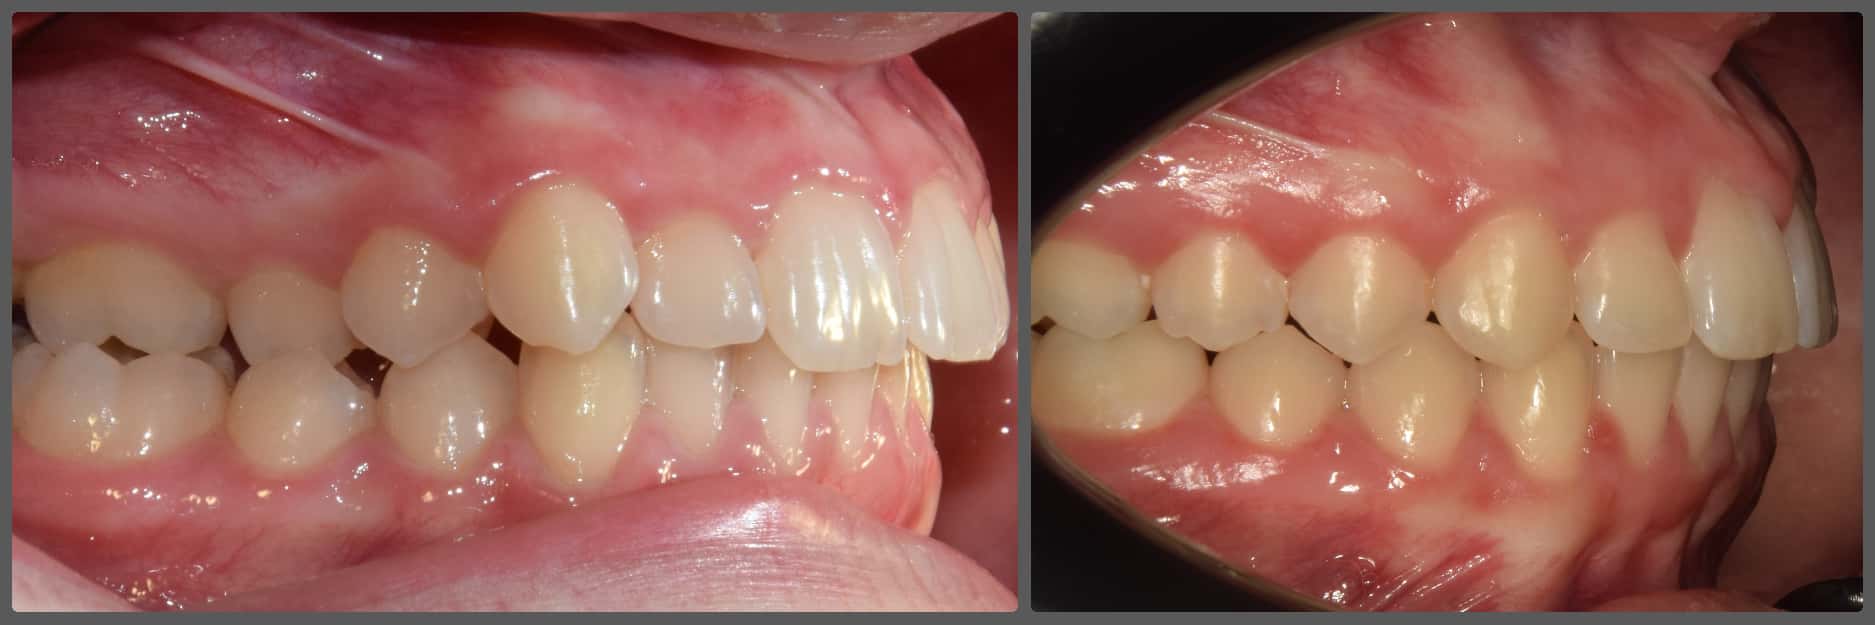

Bálint a 90 fokban elfordult jobb felső kismetszője miatt keresett meg engem. A vizsgálatokat követően kiderült, hogy a probléma ennél jóval komplexebb: súlyos keresztharapást, súlyos mélyharapást és felső rágósík billenést diagnosztizáltam nála. Alsó-felső H4 önligírozó fogszabályozó készülék, intermaxilláris gumihúzás és elülső harapásemelők segítségével korrigáltuk az eltéréseket. A bal oldali rágósík billenést fogszabályzási miniimplantátum alkalmazásával oldottuk meg. A bal felső-elülső fogakat felfelé mozgattuk, a miniimplantátumhoz húzva. Bálint esete igen komplex volt, ám kiváló együttműködésének köszönhetően 26 hónap alatt végeztünk a kezelésével (beleértve a 2-3 hónapos COVID-19 miatti leállást is). Az eredmény úgy gondolom magáért beszél!